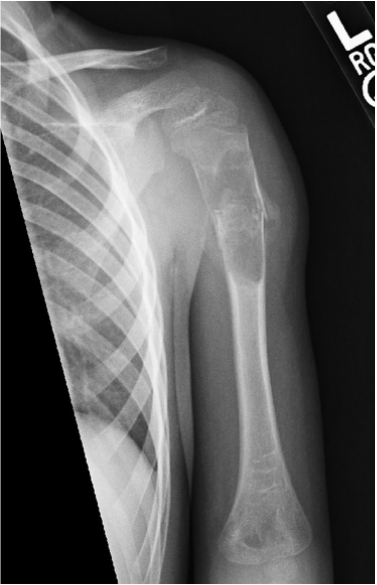

1. What is the differential diagnosis?

Simple bone cyst

Fibrous dysplasia

Aneurysmal bone cyst

Enchodroma

Eosinophilic granuloma

Brodies abscess

Brown tumor of hyperparathyroidism

2. What is the diagnosis?

The diagnosis is a pathologic fracture through a simple bone cyst.

Simple bone cysts, aka unicameral bone cysts, are a fluid-filled cavity within the bone and are most commonly found in the immature skeleton. The etiology is unknown, although it has been speculated they arise from growth disturbance to synovial tissue around a joint or venous congestion. They are benign and usually painless, although they can weaken the bone which predisposes to fracture. SBC's are most commonly found in long tubular bones however others like the talus, calcaneus, and ilium have been described. X-ray findings are a characteristic well defined, mildly expansile lesion with a sclerotic margin, intact cortex, and no soft tissue mass. There is no periosteal reaction unless a healing fracture is present. If radiographs are equivocal then MRI may be performed for confirmation.